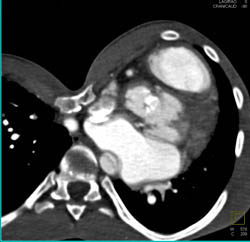

Diagnosis

Pectus Deformity